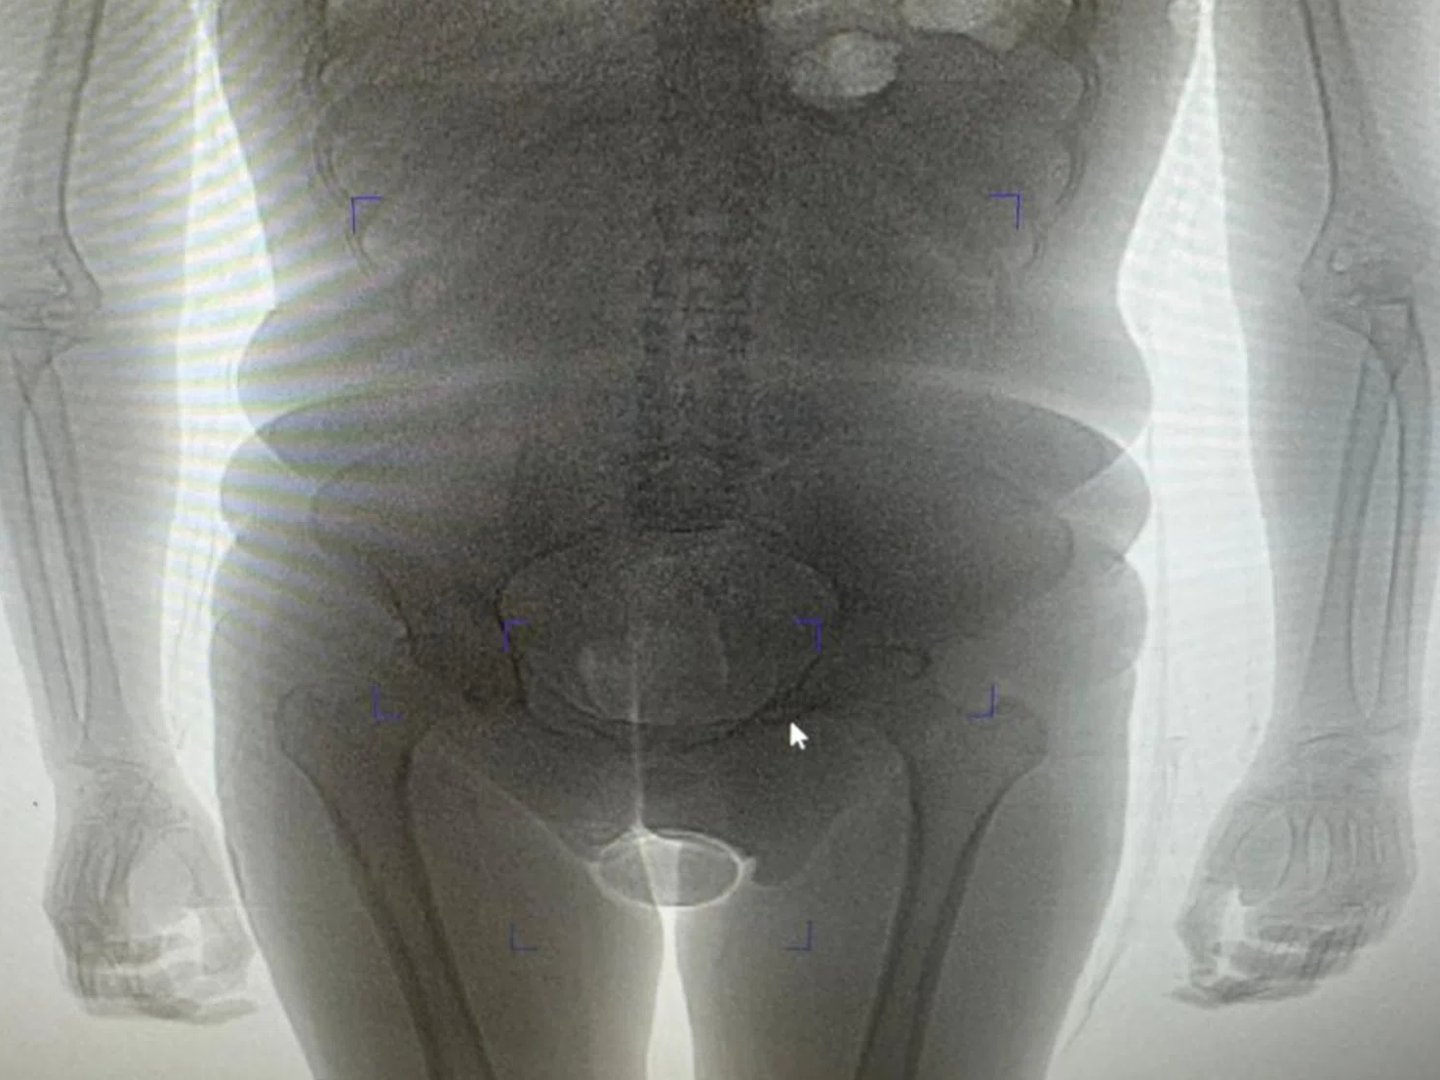

«В результате проведения таможенного досмотра обнаружено два презерватива с порошкообразным веществом внутри, один из которых находился в нижнем белье пассажирки, второй сокрыт внутриполостным способом», — говорится в заявлении пресс-секретаря. Информация есть в распоряжении URA.RU.

Девушка пояснила, что вещество представляет собой кокаин, который она согласилась перевезти по просьбе неустановленного мужчины за денежное вознаграждение. Проведенная экспертиза подтвердила, что изъятое вещество является кокаином общей массой 250 граммов. Сейчас иностранка заключена под стражу. В отношении нее возбуждено уголовное дело по статье о контрабанде наркотических средств в особо крупном размере. Санкция данной статьи предусматривает лишение свободы на срок от 15 лет до пожизненного заключения с возможным штрафом до одного миллиона рублей.